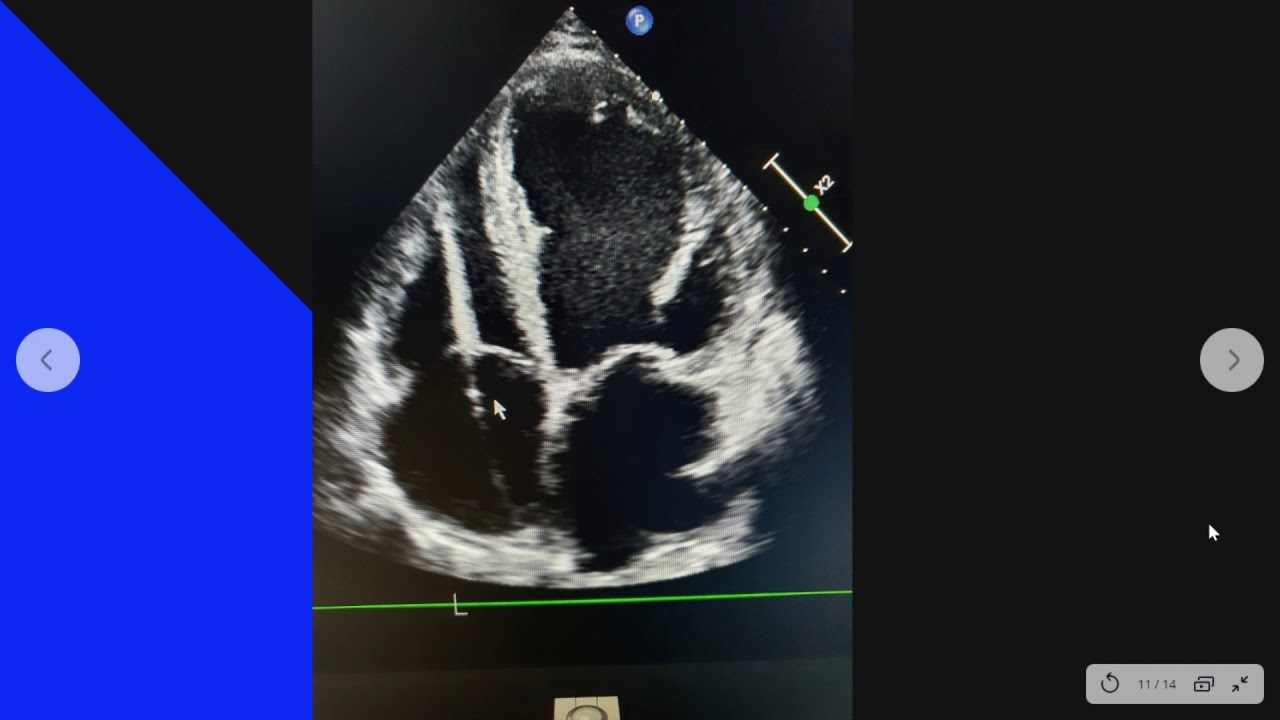

En este vÃdeo realizamos una breve descripción de los aspectos generales de los marcapasos y otros dispositivos cardioimplantables. Realizamos una descripción práctica de un tema complejo y extenso, esperamos que os guste!